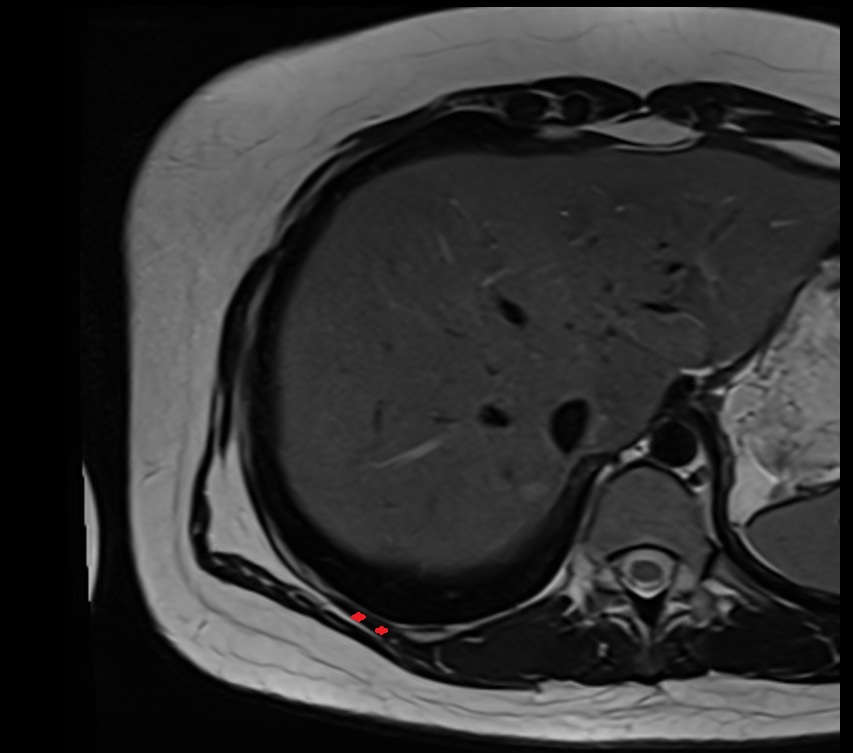

- Head of femur

- Neck of femur

- Hip joint